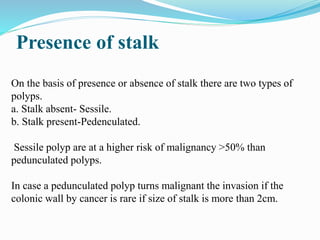

This document discusses colorectal polyps. It defines polyps and describes their types, including neoplastic and non-neoplastic polyps. It discusses adenomatous polyps in depth, noting their malignant potential increases with size over 1cm and villous architecture. Radiological diagnostic methods for polyps including single and double contrast barium enema and CT colonography are explained. The document provides an overview of polyp pathogenesis and genetic syndromes like FAP that increase cancer risk.